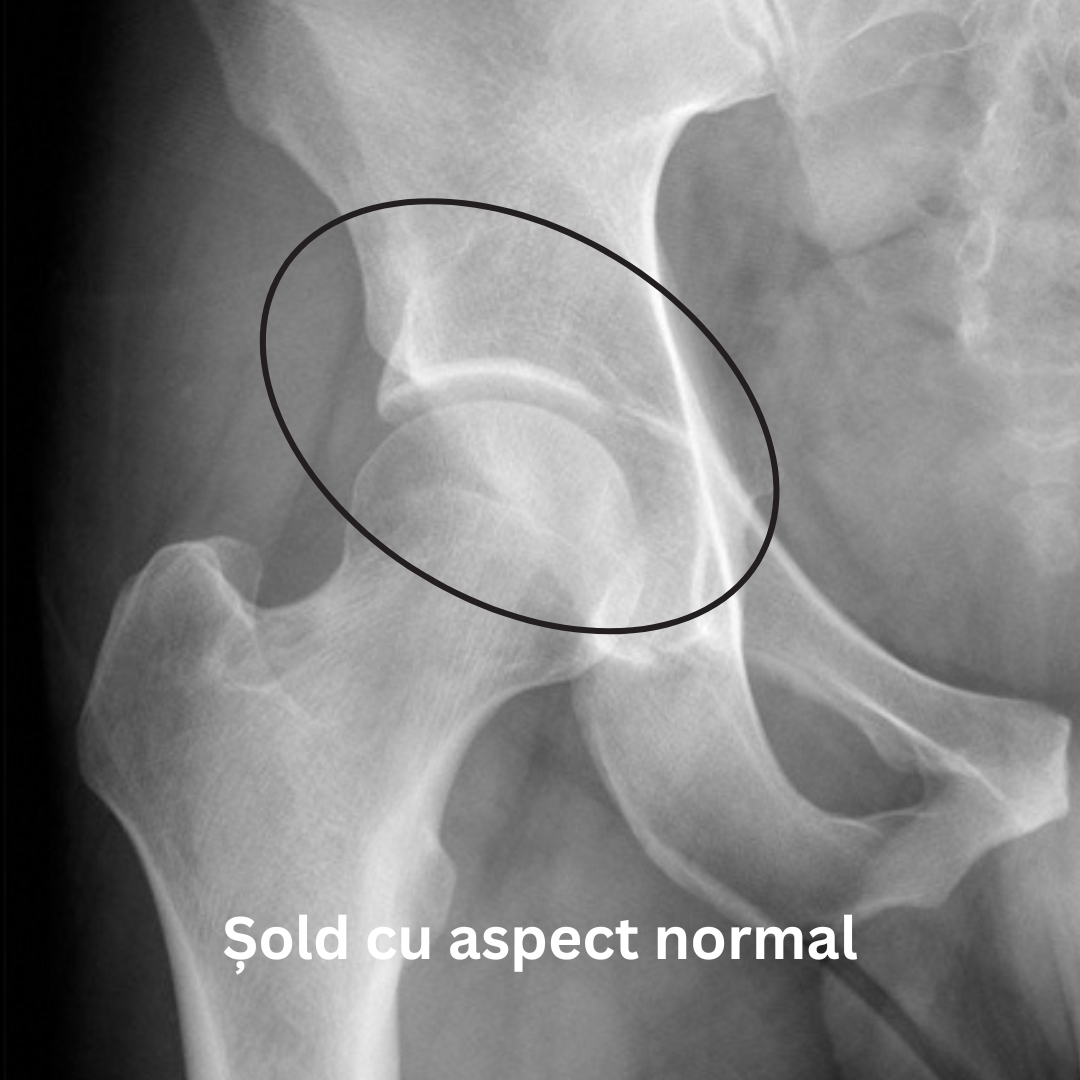

Radiografia unui șold artrozic poate arăta o îngustare a spațiului articular, modificări ale osului, precum și formarea de osteofite (imaginea din dreapta).

În cazul unui șold sănătos cartilajul articular are o suprafață netedă. Însă în situația în care apar anumite boli ale șoldului, cartilajul articular se deterioreză, iar un contact neted nu mai poate fi posibil.